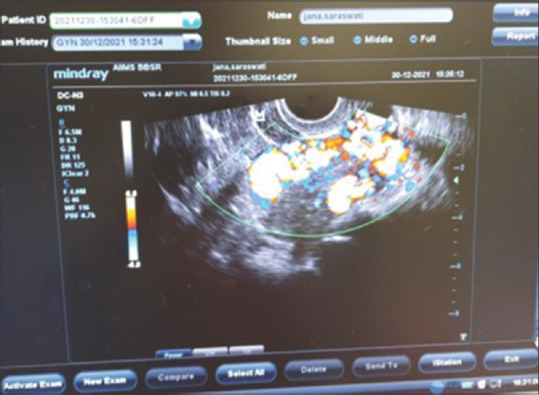

子宫动静脉畸形(UAVM)是一种罕见的发生在绝经后妇女。我们对文献的回顾显示,在这一人群中,只有少数记录在案的UAVM病例。这些患者的治疗选择包括子宫动脉栓塞(UAE)、医疗管理和子宫切除术。我们遇到了一个54岁的妇女,绝经9年,在绝经前3个月有出血史。影像学检查证实了UAVM的存在。尽管尝试了阿联酋手术,但手术失败了,因此决定进行子宫切除术,并一丝不苟地注意尽量减少失血。值得注意的是,在绝经后妇女中,子宫切除术可能并不总是能取得良好的结果,因此强调子宫切除术作为一种安全的替代治疗选择,没有任何术中过多出血。

Uterine arteriovenous malformation (UAVM) is an infrequent occurrence among postmenopausal women. Our review of the literature revealed only a few documented cases of UAVM in this demographic. Treatment options for these patients encompass uterine artery embolization (UAE), medical management, and hysterectomy. We encountered a case involving a 54-year-old woman, postmenopausal for 9 years, who presented with a history of postmenopausal bleeding over the preceding 3 months. Imaging studies confirmed the presence of UAVM. Despite an attempted UAE, the procedure proved unsuccessful, leading to the decision to perform a hysterectomy with meticulous attention to minimizing blood loss. Notably, UAE may not consistently achieve favorable outcomes in addressing UAVM in postmenopausal women, thereby underscoring the consideration of hysterectomy as a safe alternative - treatment option without any excessive intraoperative bleeding.